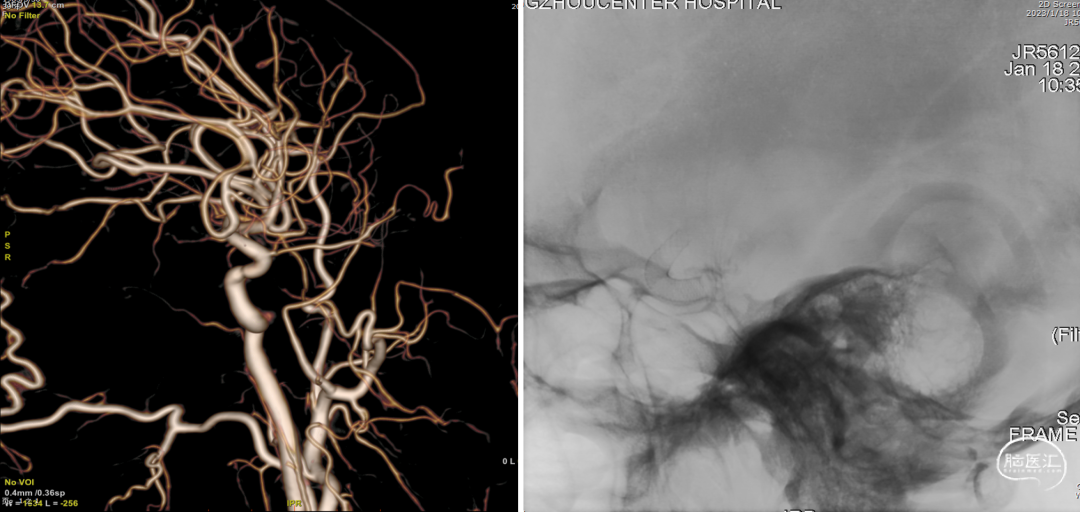

术前CTA

全脑血管造影(2022-04-13)

右颈内动脉3D重建(海绵窦段宽径7.2mm)

全脑血管造影

左颈内动脉3D重建图像(眼段宽径7.8mm)

左颈内动脉3D重建图像(海绵窦段宽径6.5mm)